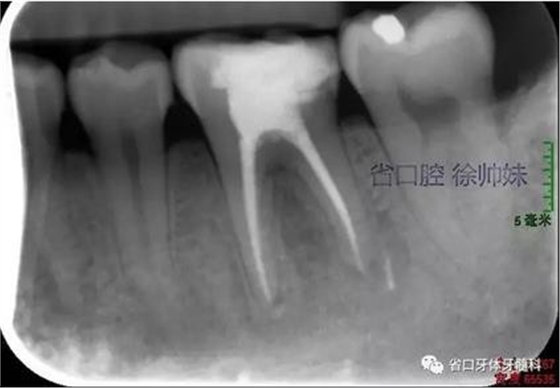

圖1 術(shù)前4月的根尖片

根尖片(圖2)示36大面積充填物近髓,根尖周及根分叉大面積低密度影。

圖2 術(shù)前根尖片